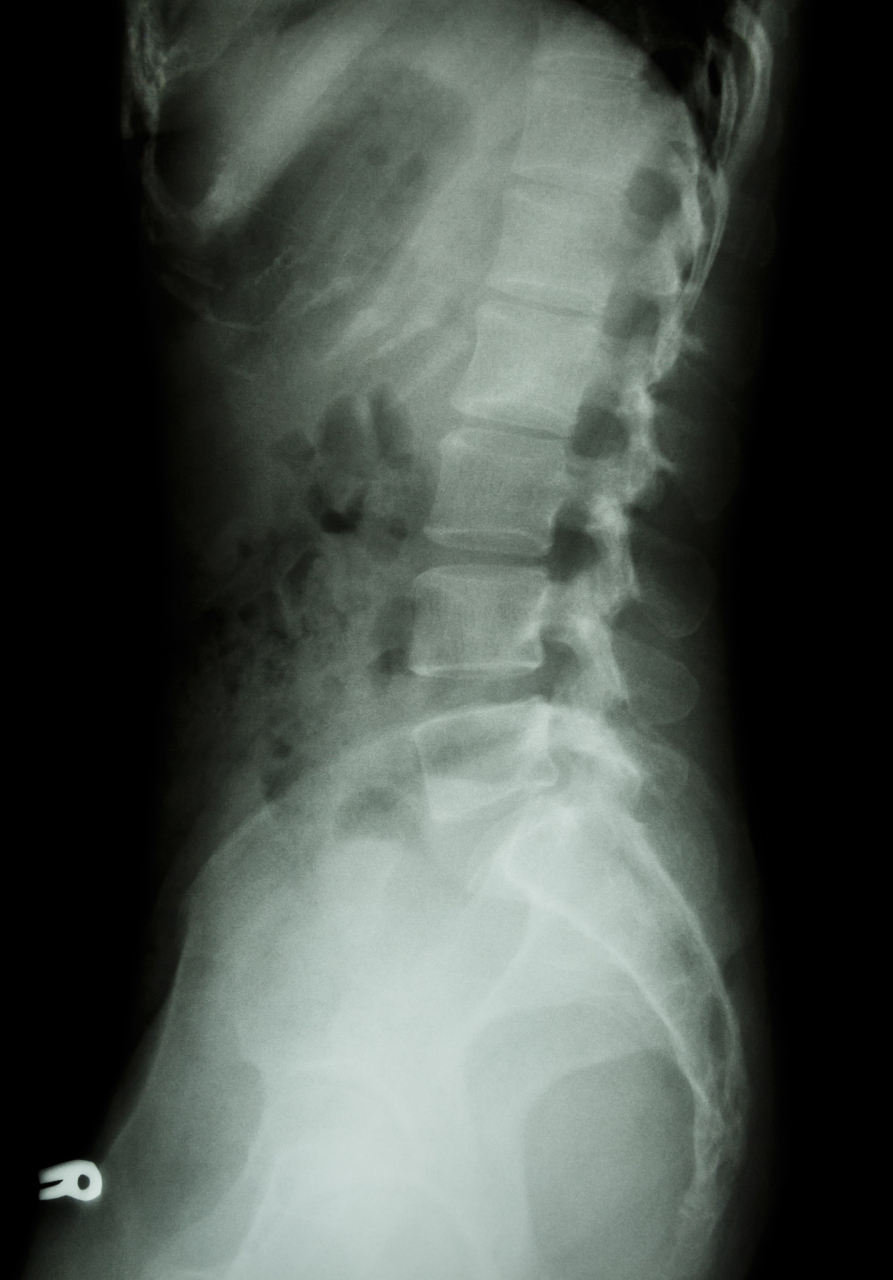

这是一个患者刚拍的腰椎滑脱的x光片,与5年前x光对比没有加重.

腰5椎体滑脱症

腰椎x光片显示:腰5椎体滑脱,腰5双侧椎弓峡部裂.